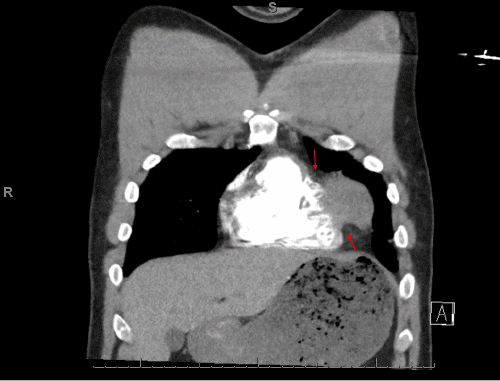

Initial workup revealed ST elevations in the anterolateral leads and a peak troponin of 43.74 µg/L. Coronary angiography demonstrated subtotal occlusion of the apical left anterior descending (LAD) and first diagonal (D1) arteries (Figure 1). Percutaneous coronary intervention (PCI) with stenting of the mid-LAD and balloon angioplasty of the D1 was performed. However, significant residual compressive lesions persisted in both arteries.

Figure 1. Coronary Angiogram. Published with Permission

Note severe stenosis in the apical segment of the LAD artery (arrow). The occluded diagonal branch is poorly visualized in this projection.